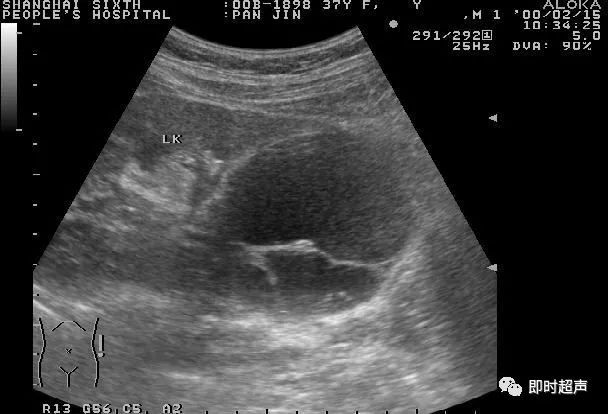

3.肾盂旁囊肿(parapelvic cyst) 位于肾窦回声内,容易压迫肾盂或肾盏,造成肾积水(图4-1-9)。

图4-1-9 肾盂旁肾囊肿声像图